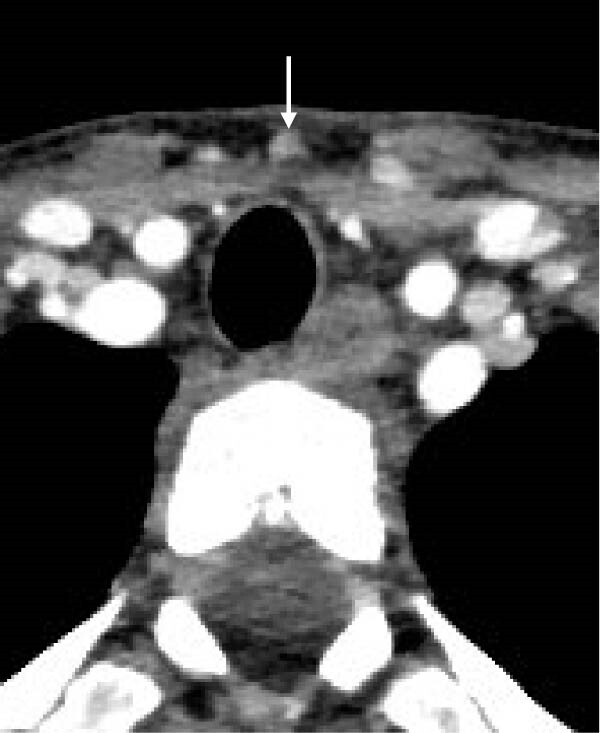

В то же время, во время сцинтиграфии паращитовидных желез с 99мТс-МИБИ не было отмечено накопления препарата. Далее была проведена четырехмерная компьютерная томография (4D КТ), которая не показала наличия глубоких узлов в средостении (рис. 8-11)). По результатам обследования был исключен синдром множественной эндокринной неоплазии (МЭН), хотя семья отказалась от генетического тестирования.

Рисунки 8-11. Снимки 4D КТ в поперечной (8,9), сагиттальной (10) и коронарной (11) плоскостях, где заметны слегка контрастируемые узелки в претрахеальной подкожной клетчатке (8-10) и в нижнем полюсе левой доли щитовидной железы (11). Размеры варьируют от 3 до 12 мм.